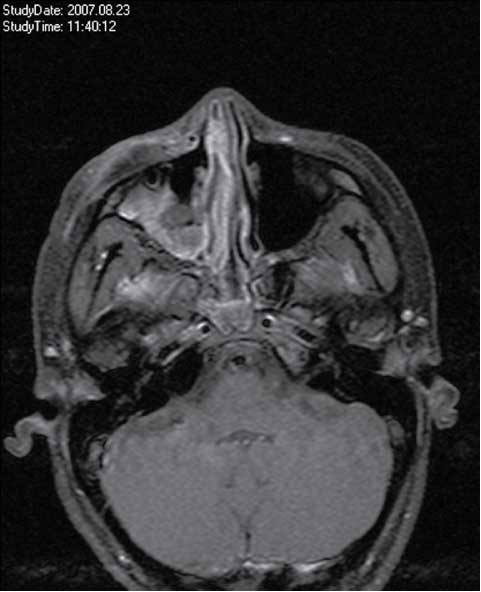

A 15-year-old previously healthy primigravida was admitted to the Department of Ophthalmology with a 3-day history of ocular protrusion and loss of vision in the right eye (Figure 1). When pregnancy was diagnosed, she was transferred to the obstetrics department for further evaluation and management.

Retrobulbar hemorrhage at the right eye.

To characterize the ophthalmologic complications, magnetic resonance imaging was performed, which revealed an extraconal intraorbital hemorrhage with elongation of the ocular bulb and stretching of the optic nerve. Therefore, an immediate surgical intervention (i.e., orbital decompression) was performed (Figure 2).